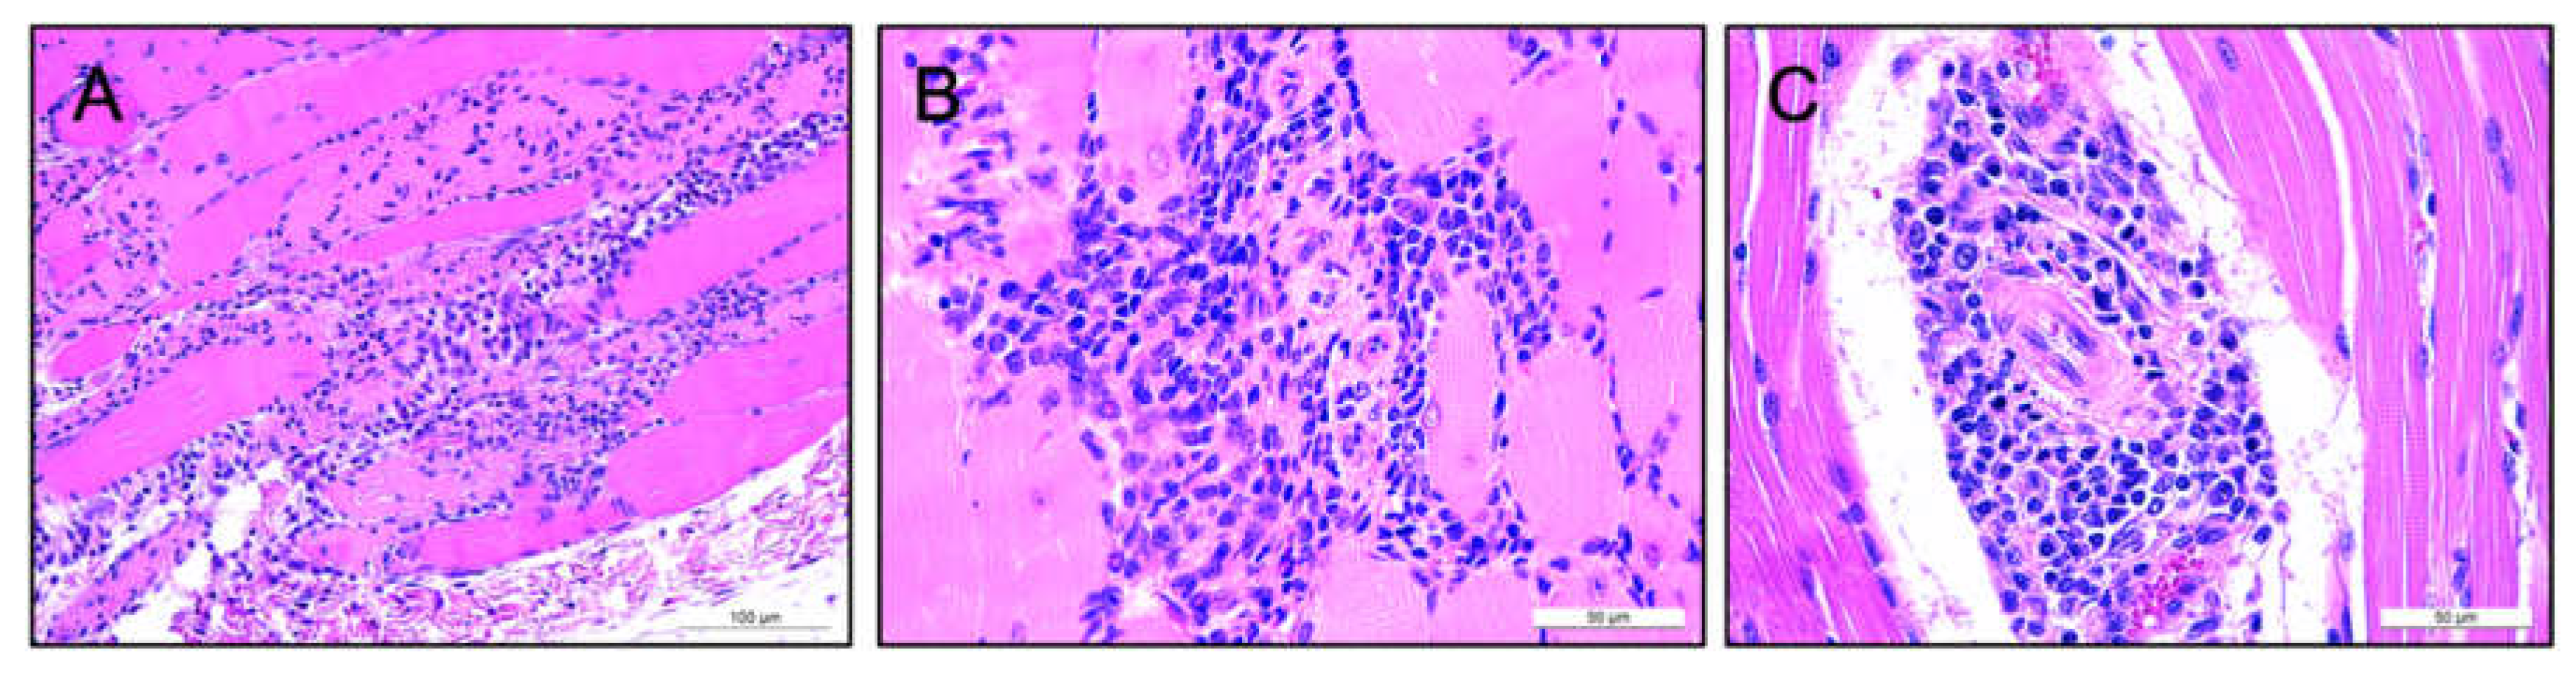

3.4. Lack of Pathology Observed in Murine and Ovine Models Following Intramuscular AAV-mAb Administration

3.5. Human IgG Is Expressed in Murine and Ovine Muscle